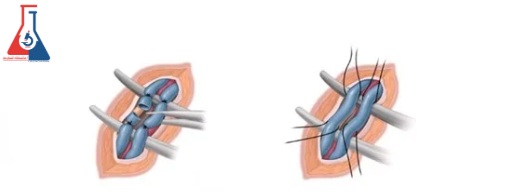

هدف از جراحی بستن ورید آسیب دیده برای هدایت جریان خون به وریدهای سالم است. این امکان پذیر است زیرا دو سیستم شریان و ورید دیگر گردش خون را به کیسه بیضه و از کیسه بیضه تامین می کنند.

روش های جراحی

جراح شما می تواند با بخیه زدن یا بستن ورید (بسته شدن) جریان خون را از طریق سیاهرگ بیضه متوقف کند. امروزه معمولا از دو رویکرد استفاده می شود. هر دو نیاز به بیهوشی عمومی دارند و روشهای سرپایی هستند که معمولاً به شما امکان میدهند همان روز به خانه بروید. رویه ها عبارتند از:

واریکوسلکتومی میکروسکوپی جراح یک برش کوچک در پایین کشاله ران ایجاد می کند. جراح با استفاده از یک میکروسکوپ قدرتمند، چندین ورید کوچک را شناسایی کرده و میبندد. این روش معمولاً ۲ تا ۳ ساعت طول می کشد.

واریکوسلکتومی لاپاراسکوپیک. جراح این عمل را با استفاده از دوربین فیلمبرداری و ابزارهای جراحی متصل به لوله هایی که از چند برش بسیار کوچک در قسمت تحتانی شکم عبور می کند، انجام می دهد. از آنجایی که شبکه وریدها در بالای کشاله ران پیچیدگی کمتری دارند، وریدهای کمتری برای بستن وجود دارد. این روش معمولا ۳۰ تا ۴۰ دقیقه طول می کشد.